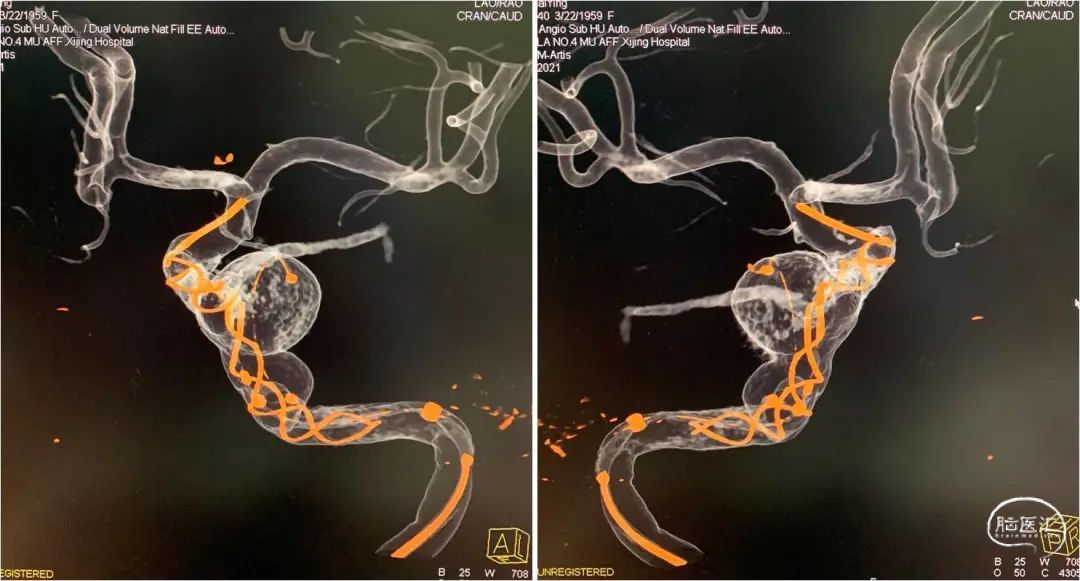

时全星教授:tubridge03治疗颈内动脉c3-c4段多发大动脉瘤一例